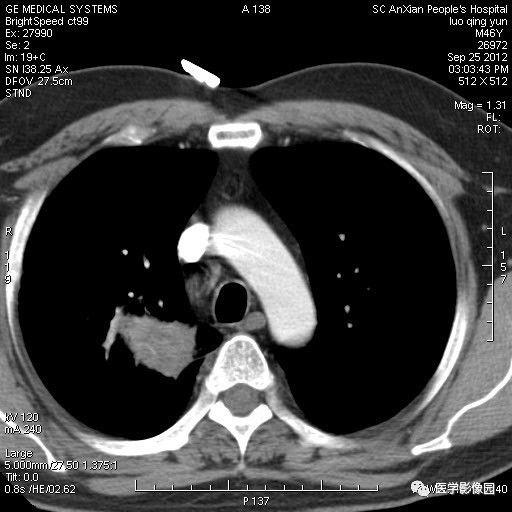

影像学表现:右上肺见不规则团块状高密度阴影,略有分叶级毛刺,边缘模糊,邻近胸膜增厚,增强扫描呈轻中度强化。

诊断结果:右上肺炎性假瘤

本病影像学表现无绝对特征性。单发多见,多位于肺表浅部位,多呈圆形或椭圆形,直径多在2-5cm或更大;多有假包膜,边缘多清晰光整,有时也毛糙,并可有分叶或毛刺;邻近胸膜局限性增厚、牵拉,病灶边缘呈桃尖样突起即桃尖征(尖端指向胸膜);增强扫描多呈中度均匀强化,持续时间较长。亦可显著强化。